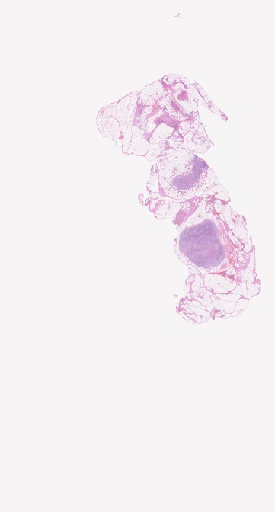

Pathology Image Library

ARUP Laboratories®